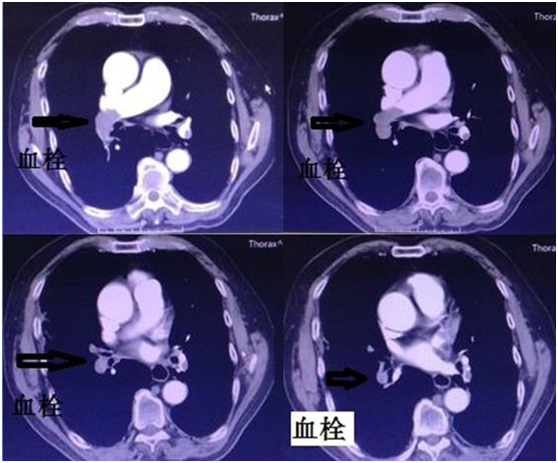

2例患者中1例为肺癌患者,另1例为胰腺癌患者,均表现为呼吸困难、活动时加重,1例伴有晕厥。行CTA检查示:肺动脉栓塞。急诊行肺动脉碎栓+溶栓术,术后第1天患者临床症状明显缓解,术后7天康复出院。

朱亮副主任医师指出:肺栓塞在临床中并不少见,特别是在肿瘤科。肺栓塞并不可怕,关键要及时诊断,及时治疗。在西方国家,一般人群的肺栓塞年发病率是1‰~3‰,而恶性肿瘤使其发病率增加4倍。有流行病学资料表明,栓塞是第二位导致肿瘤患者死亡的原因,仅次于恶性肿瘤本身。栓子主要来自静脉系统血栓。阻塞范围超过肺动脉内径的50%~70%者容易导致猝死。猝死原因是肺动脉高压,右心衰竭、心排血量锐减、脑及冠状动脉血流减少、缺氧及不可逆性休克。肺栓塞的治疗方法颇多,介入治疗是最有效的方法,因其安全、有效、微创、成功率高易被患者所接受。用一根1mm粗的导管选插至肺动脉血栓处,搅拌血栓使其粉碎,然后在留置导管于血栓处,注入溶栓药物将血栓溶解。此方法局部药物浓度高,血栓溶解快,尿激酶用量少,安全、可靠。